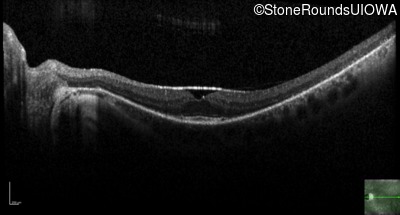

The clinical features supporting the diagnosis of MAK-associated autosomal recessive retinitis pigmentosa in this patient include: night blindness and constricted visual fields (with temporal predilection) as his earliest symptoms; bone-spicule-like pigmentation (with nasal predilection) and narrowed arterioles on fundus examination; loss of outer retinal structures on OCT; a similarly affected sibling; Jewish ethnicity; and, normally sighted parents.

Age at visit: 55 years